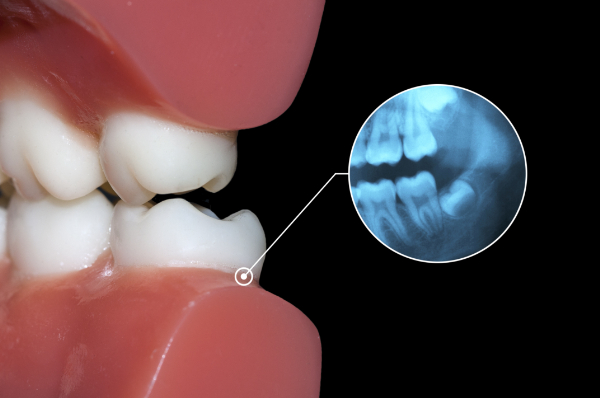

検査

抜歯前には、検査を行います。レントゲン撮影やCT撮影を行い、親知らずの生え方や神経・血管との位置関係を把握します。この検査によって親知らずを抜歯する難易度を判断し、当日の流れや麻酔方法を患者さまと共有することで、安心して処置を受けられる体制を整えます。